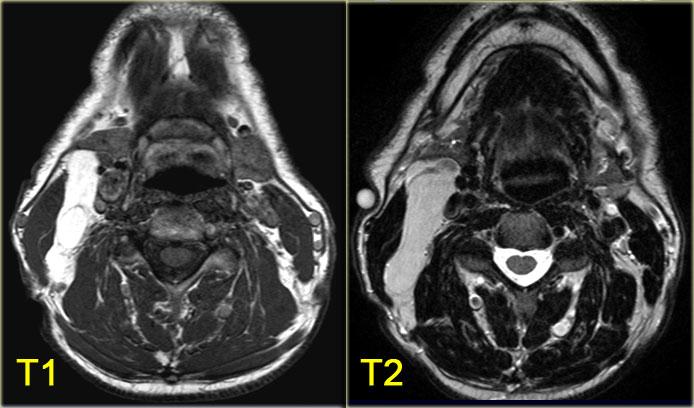

U mỡ

Bên trái là hình ảnh của một bệnh nhân có sưng nề ở phía sau bên trái cổ.

Hình ảnh MRI tại mức xương móng.

Tổn thương nằm trong khoang cổ sau.

Trong trường hợp này, việc phân tích các thành phần giải phẫu bình thường của khoang cổ sau có thể được rút gọn.

Khối có tín hiệu tương đương mô mỡ trên chuỗi xung T1W và tín hiệu bị xóa hoàn toàn khi áp dụng kỹ thuật xóa mỡ.

Không có hình ảnh ngấm thuốc (không trình bày), do đó có thể kết luận đây là u mỡ.

Bên trái là hình ảnh chuỗi xung T1W và T2W của một bệnh nhân khác có u mỡ.